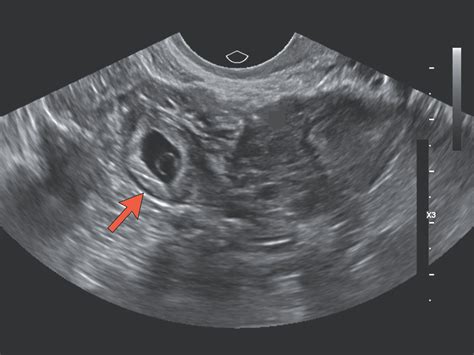

The diagnostic criteria for ectopic pregnancy involve a combination of clinical presentation, ultrasound imaging, and laboratory tests, including HCG levels. The American College of Obstetricians and Gynecologists (ACOG) recommends that women with suspected ectopic pregnancy undergo transvaginal ultrasound to visualize the gestational sac. If the HCG level is above the discriminatory zone (typically around 1,500-3,000 mIU/mL), and no intrauterine pregnancy is seen on ultrasound, ectopic pregnancy should be suspected.